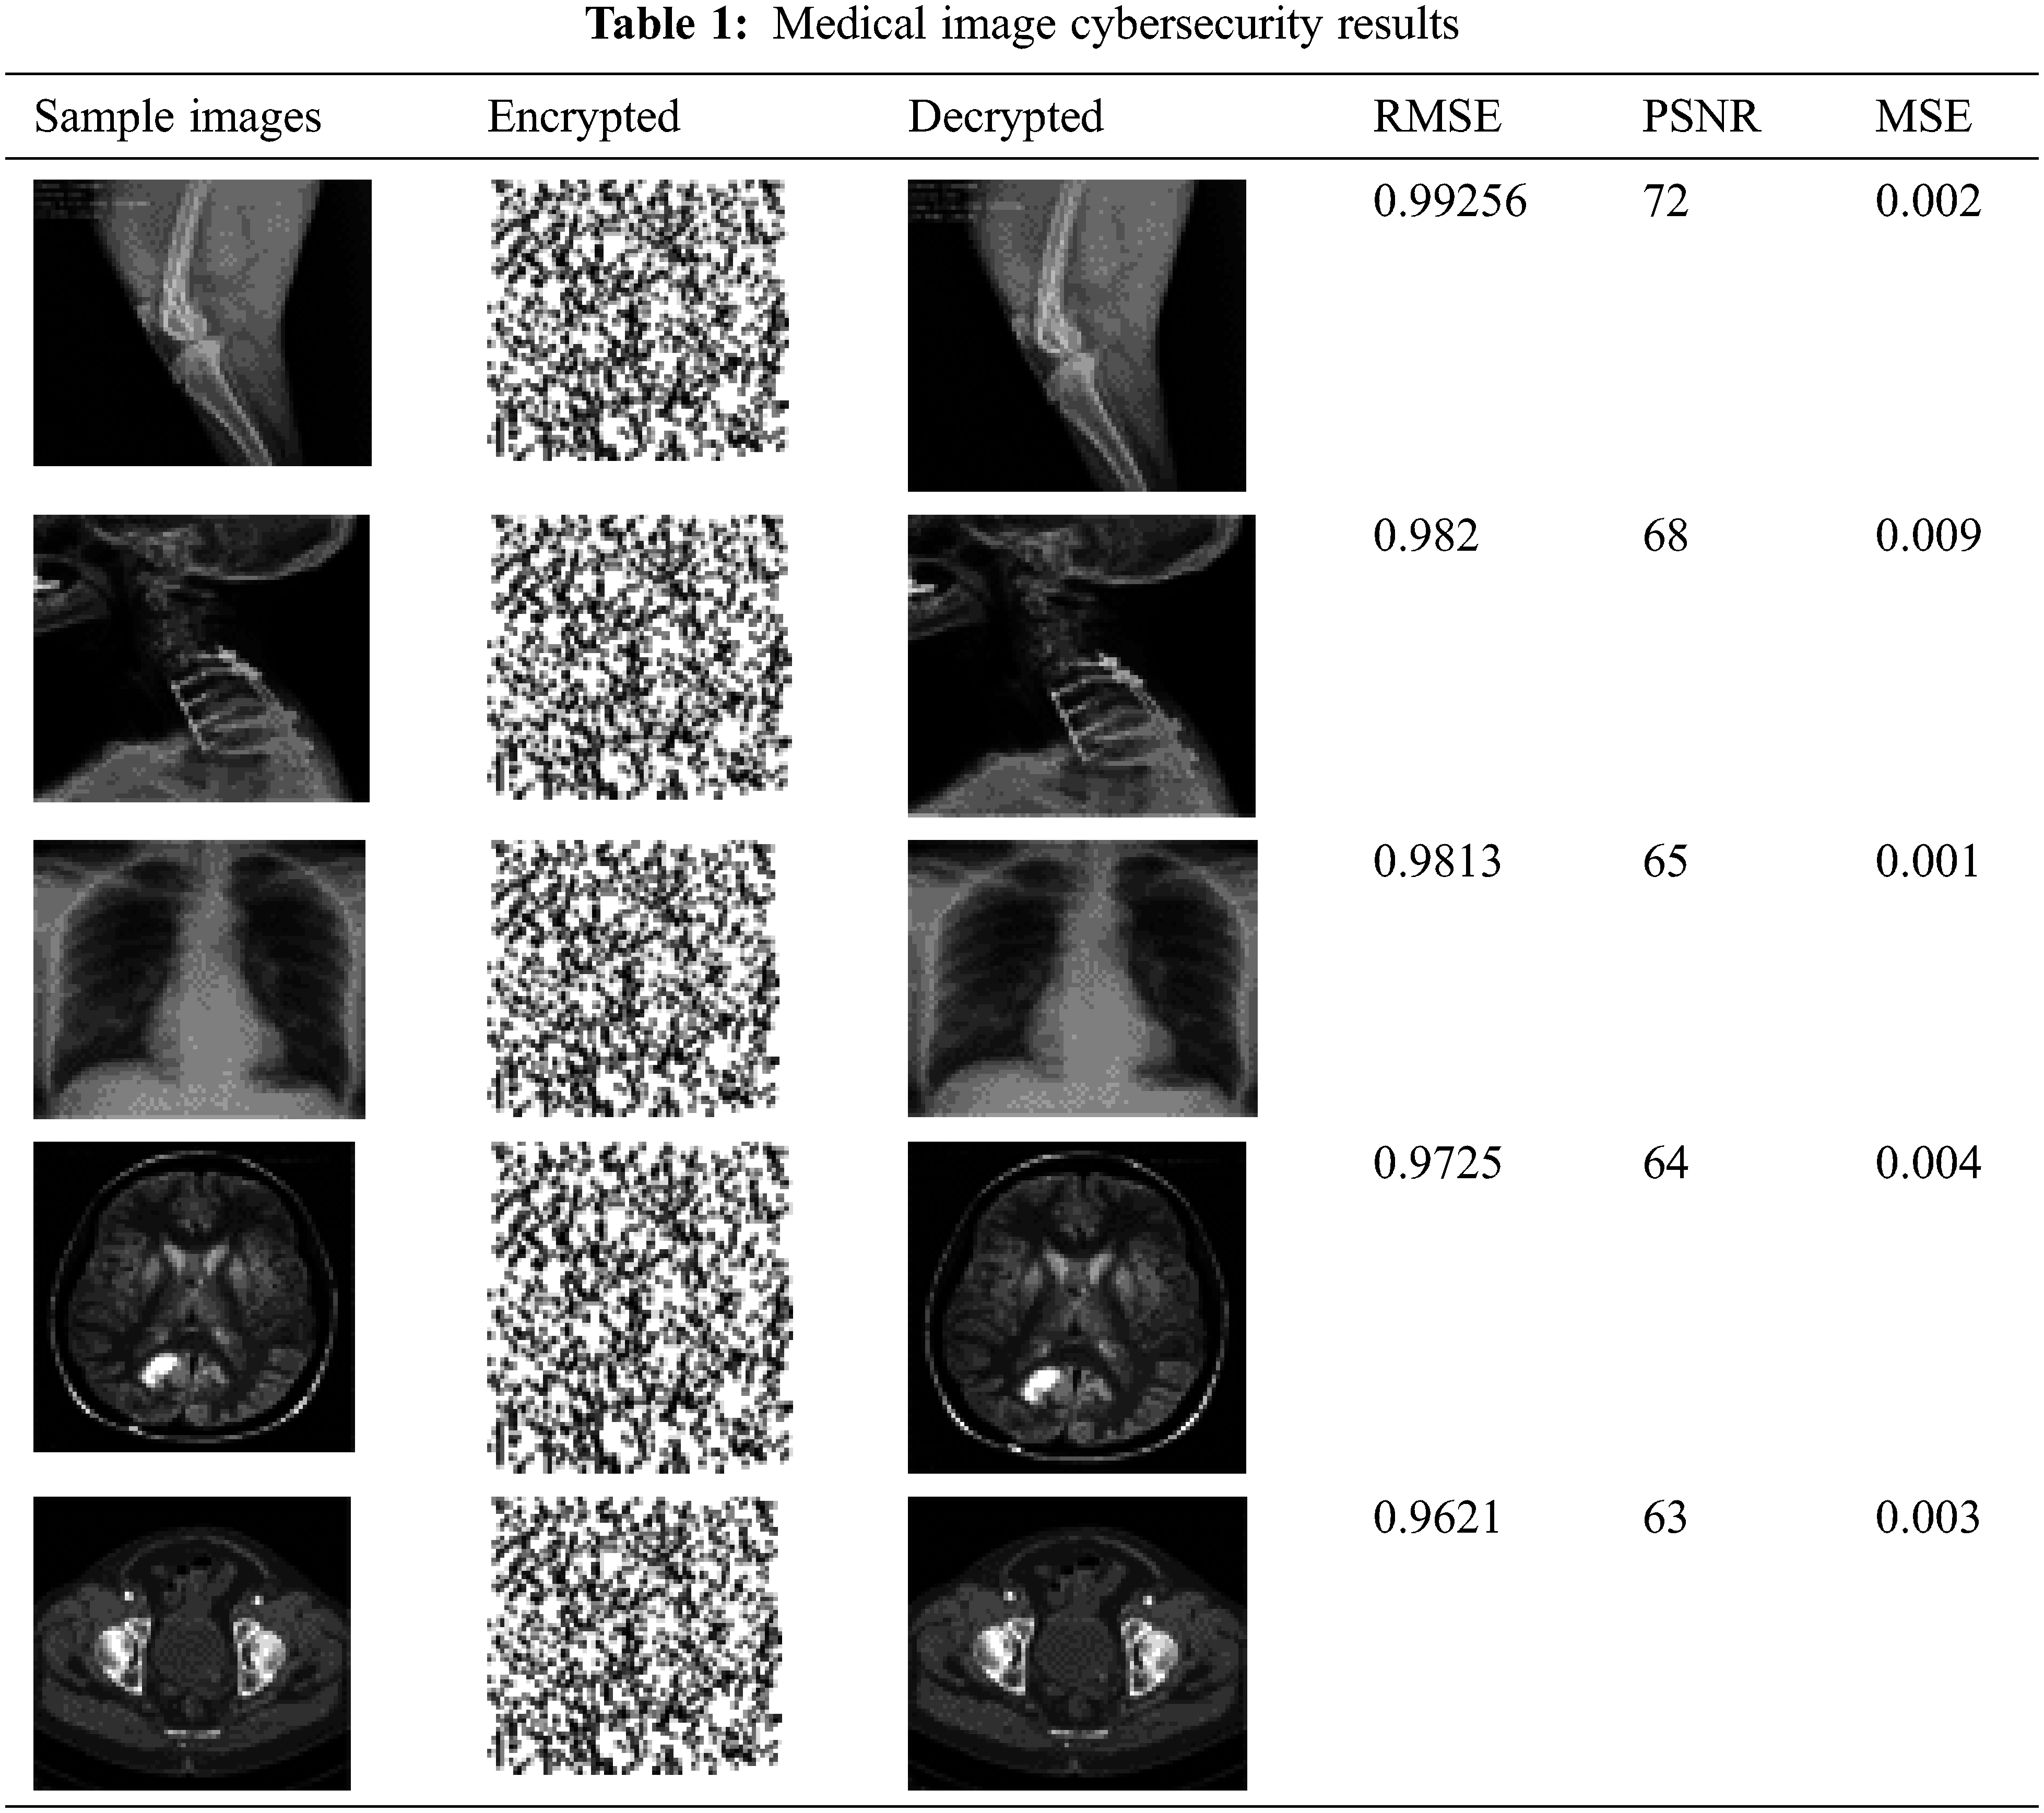

Consider five sample medical images for the performance analysis of proposed LGE-HES model in healthcare system. The sample medical images cybersecurity improved results are demonstrated in Tab. 1.

The performance of the proposed method has been compared with the different conventional methods such as Signcryption + (Adaptive Elephant Herd Optimization) AEHO [35], OHE [29] and ODLSB [31] in terms of PSNR, RMSE, MSE, Encryption time, Decryption time, key braking time, key size. The PSNR value obtained from the proposed method is compared with the conventional methods are demonstrated in Fig. 2. The integrity of a transmitter transmission is affected by the ratio between its highest achievable strength and the power of degrading noise is defined by PSNR. The comparisons of medical image security systems such as Signcryption +AEHO, OHE, and ODLSB are among the encryption methods are employed. The PSNR assessment in the suggested technique is improved more than the other existing methods. In a 250 kb picture, the PSNR in the suggested version is 63 dB, which is the highest among the different techniques. Although a greater PSNR value is typically suggests a higher-quality secured image reconstruction. MSE is a technique for determining how close estimations or projections are to actual values. The comparative analysis of proposed MSE value over the conventional methods is illustrated in Fig. 3.

Most particularly, the performance analysis from Tab. 7 for the large scale of 250 kb data size has adopted supreme consequences. The proposed LGE-HES method has attained high PSRN value, key braking time, RMSE, key size and very less encryption time, MSE, and decryption time over the conventional Signcryption +AEHO, OHE, and ODLSB methods. The proposed method has achieved higher PSNR value (63 dB) over the conventional methods such as 54, 42 and 50 dB. As a result, the overall evaluation demonstrates that the generated model performs better in cybersecurity when using the optimization-assisted encrypted approach.

In this research analyzed the cybersecurity of blockchain technology in healthcare system with the supreme encryption system, the non-public key, and the general public key are optimized using the LGE-HES methodology. Moreover, PSNR, MSE, RMSE, encryption time, decryption time, key size, and key braking time are used to assess the suggested approach’s performance. The maximum PSNR is 63 dB, the minimum MSE is 0.003, and the encryption and decryption times are 69 and 76.09 ms, respectively, ac-cording to the implementation results. As a result, the image’s secrecy is maintained in the end, and the recovered image is made available to the data user without compromising the image’s quality. In addition, there are a number of other issues, such as the overall key size and the computation utilized in the prior technique being quite large. The hybrid optimization methodology will be considered in the future to account for the security of healthcare increasing level.